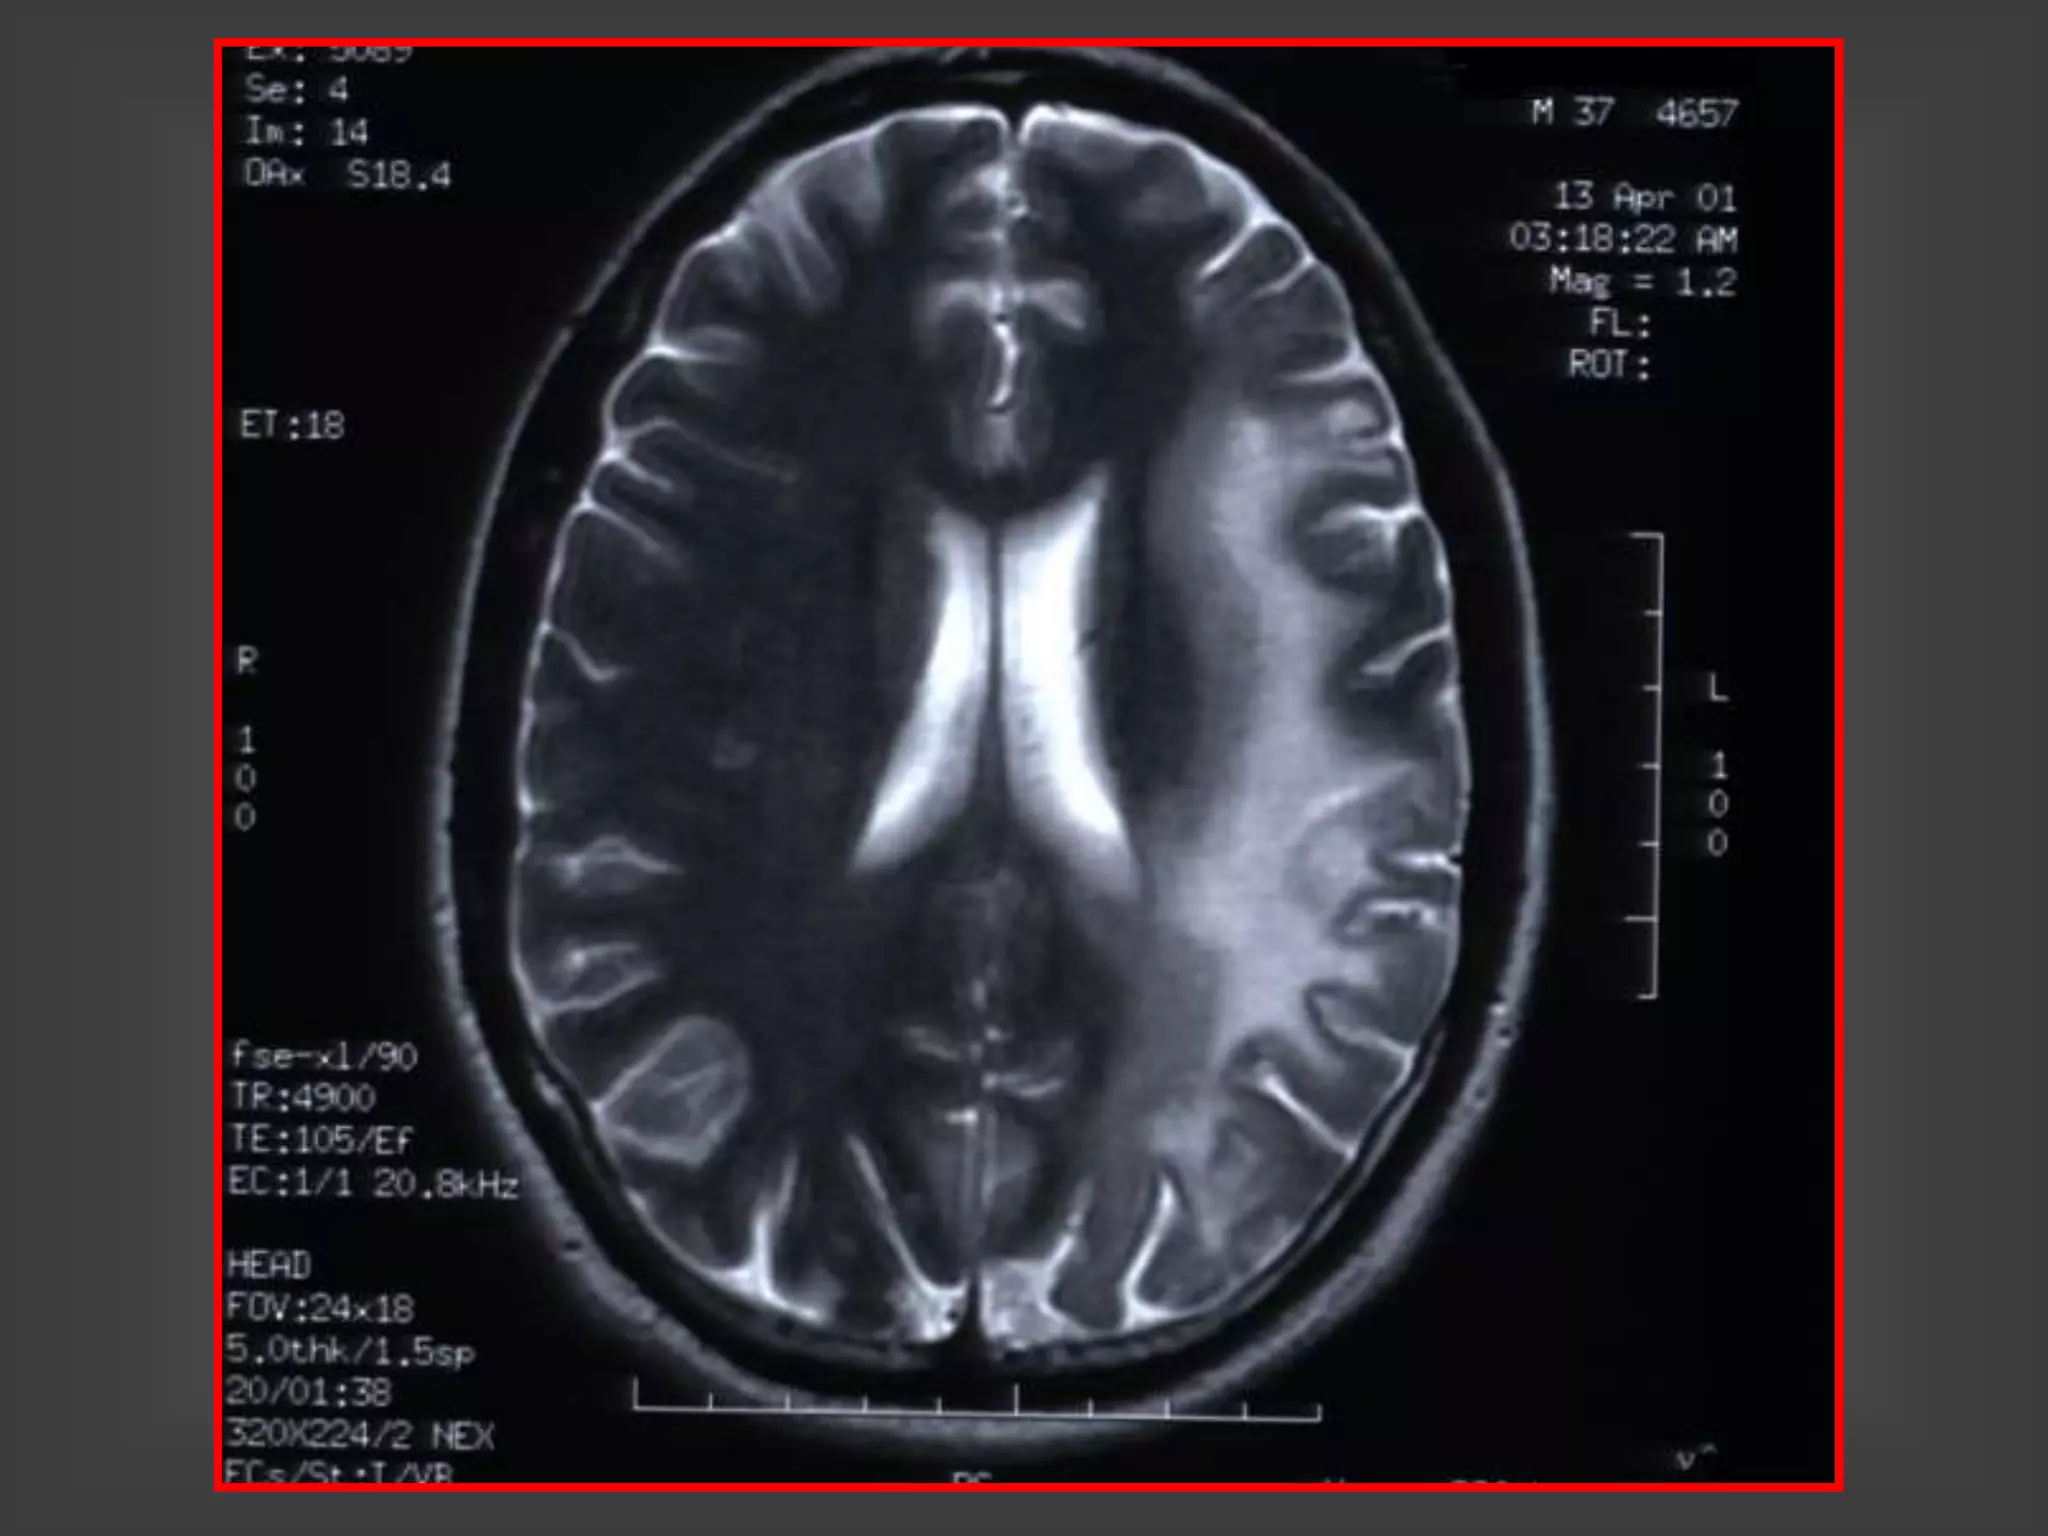

 RMN: leucoencefalopatía con periventriculitis y

ventriculitis. Refuerzo del contraste en epéndimo

y región subependimaria.

PERIVENTRICULITIS POR CMV -

RM